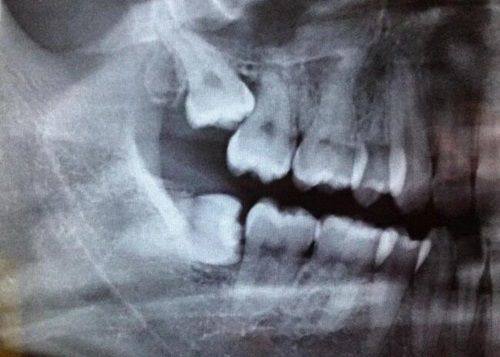

(一)成都布莱梅联合口腔医院种植牙技术介绍

成都布莱梅联合口腔医院的数字化种植体系十分精良。开展了全息种植、即刻种植、即刻负重、牙槽骨吸收严峻植骨技术、咬合重建等项目。其中,3D数字化导板种植牙技术误差控制在0.1mm以内,可实现“当天拔牙、当天种牙、当天戴冠”,大大缩短了患者的治疗周期。

5U数字化技术中的UDCO数字化根控正畸技术用于种植牙,误差能控制在1μm左右,精细度极高。此外,医院还具备穿颧穿翼种植技术,能解决牙槽骨萎缩重度患者的种植问题,这相较于传统种植技术,为更多患者带来了种植的希望。